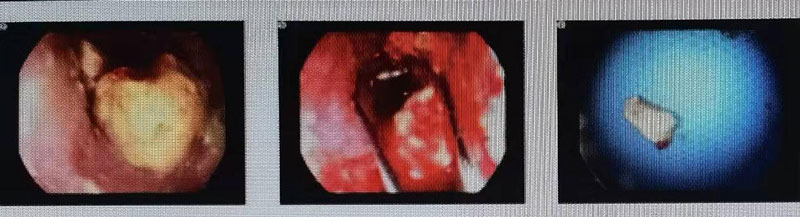

本例患者為80歲女性,確診食管鱗癌,因進(jìn)食困難在當(dāng)?shù)蒯t(yī)院給予營養(yǎng)、補(bǔ)液等對(duì)癥治療,后進(jìn)食困難進(jìn)一步加重,面湯及水均不能通過,遂就診我院腫瘤科。請消化內(nèi)科劉慶民主任行“電子胃十二指腸鏡檢查”,鏡下見:食道中段見隆起性病灶,大量食物殘?jiān)媪?,用異物網(wǎng)籃取出,內(nèi)鏡不能繼續(xù)通過。

null